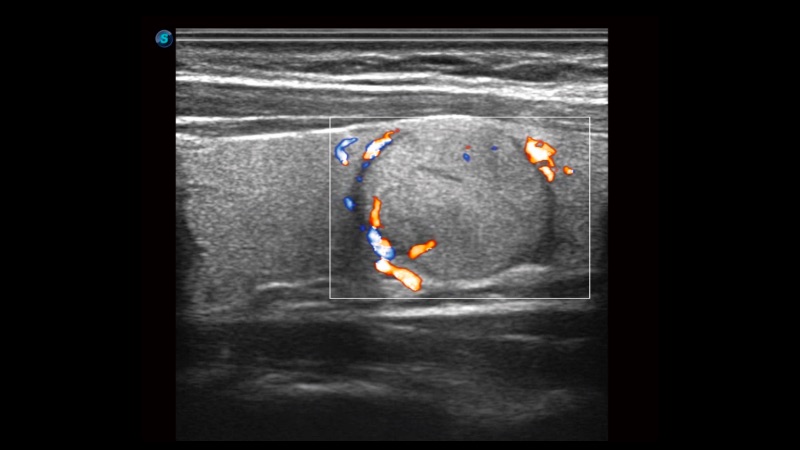

新一代微米成像技術大大提高了器官和病變的可見性。高清對比度分辨率將抑制斑點噪聲,同時保持真實的組織結構。